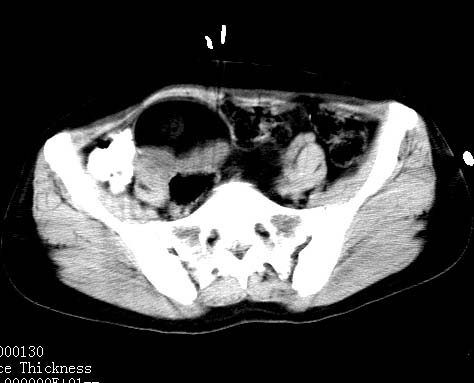

女性 病人 44岁 盆腔 下腹部痛1天!

盆腔内低密度为主混杂等密度及少许囊样与班状钙化影,如果做了肠道准备就好了。支持畸胎瘤。当然做mri会更好

典型的双侧附件畸胎瘤.

支持各位大侠观点.病人有急性腹痛,需除外有扭转可能.建议mri.

盆腔多发畸胎瘤,较为典型。